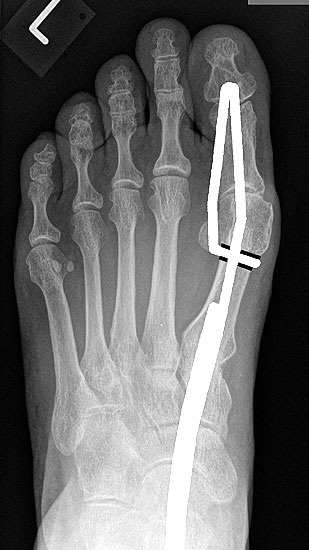

2) Rezidiv bei insuffizienter operativer Technik:

Die dorsoplantaren Röntgenaufnahmen zeigen eine Open-wedge Technik mit der normalerweise ein erhöhter intermetatarsaler Winkel gut zu korrigieren ist (Abbildung 3). Die Wirksamkeit einer Basisosteotomie ist umso größer, je proximaler diese durchgeführt wird. Je weiter distal die Osteotomie, umso geringer die Korrektur. Auf den postoperativen Bildern ist der distal unverändert große Abstand zwischen Metatarsale I und Metatarsale II erkennbar, bei gleichzeitiger Subluxation des Großzehengrundgelenks und dezentrierten Sesambeinen. Darüber hinaus finden sich initiale degenerative Veränderungen im Großzehengrundgelenk. Klinisch bestand eine hohe Weichteilspannung, bei verkürzter Extensor- und Flexor hallucis longus Sehne.  Daher wurde ein verkürzendes Verfahren zur Revision gewählt (Abbildung 4). Die Lapidusarthrodese stellt ein sehr zuverlässiges Verfahren zur Behandlung von Hallux valgus Rezidiven dar 9. Die Fusion des Tarsometatarsale-I-Gelenks kombiniert Stabilität mit einem hohen Korrekturpotenzial. Aufgrund der verfahrensimmanenten Verkürzung des ersten Strahls und der in diesem Fall bereits präoperativ vorhandenen Transfermetatarsalgie wurde die Entscheidung für eine verkürzte Weil-Osteotomie am zweiten bis fünften Strahl gefällt. Die Kombination beider Verfahren führte zu einem homogenen Metatarsale-Index und zu einer gleichmäßigen plantaren Druckverteilung 10. Die Hallux valgus interphalangeus Fehlstellung wurde mit einer Akin-Osteotomie korrigiert.